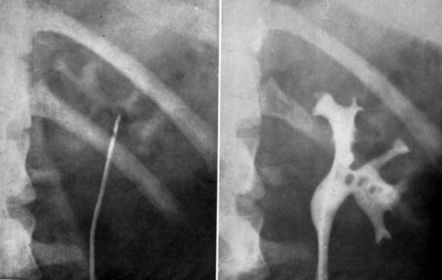

Hydronephrosis Water in the nephrons of the kidney (there is no actual water though) Results from an obstruction of the renal pelvis, calyces, and ureter due to back pressure of urine that can't flow pas the obstruction Is NOT an actual disease but results from another Occurs bilaterally in pregnancy due to fetus pushing against ureters Symptoms: hematuria, pyuria, flank pain, fever Radiographic Appearance: IVU-enlargement above the obstruction and no anatomy demonstrated below, calyces are sharp in appearance with enlargement